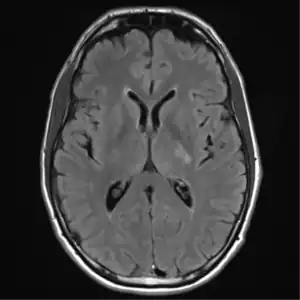

MRI brain: cryptococcus -